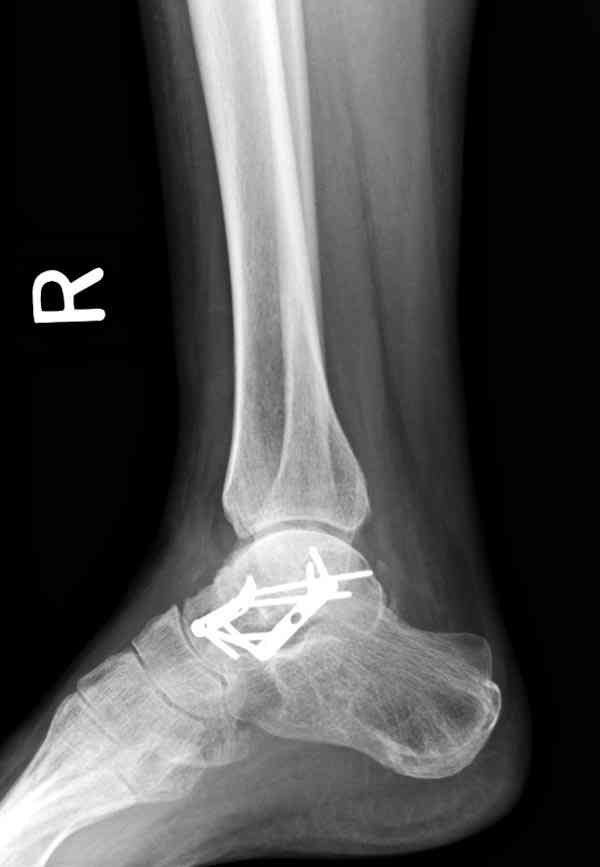

Случай с множественным оскольчатым переломом тарана оперированный из двойного доступа.

Через 2 мес.:

Через 8 мес.:

Через 14 мес.: